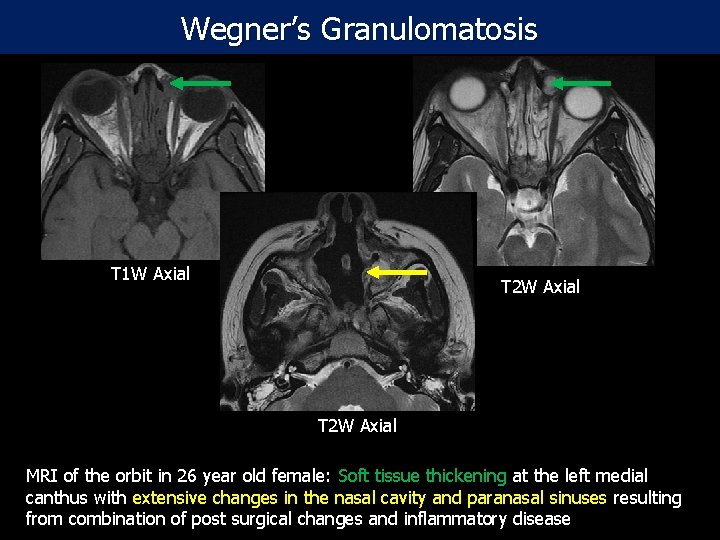

Wegner’s Granulomatosis T 1 W Axial T 2 W Axial MRI of the orbit in 26 year old female: Soft tissue thickening at the left medial canthus with extensive changes in the nasal cavity and paranasal sinuses resulting from combination of post surgical changes and inflammatory disease